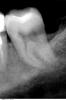

super Опубликовано 4 октября, 2011 Поделиться Опубликовано 4 октября, 2011 Здравствуйте, форумчане. 2 года решил назад поставить брекет-систему на зубы. По рекомендации ортодонта удалил восьмерку снизу слева. Удаление было довольно сложным, зуб лежал в кости, его выдалбливали молотком, резали десну. Хирург сделал настолько большую дырку/разрез в десне, что она не затянулась, до сих пор!Под впечатлениями от этого удаления, не посещал стоматолога 2 года, и вот решился. Опять хочу поставить брекеты, но непонятно, что делать с дыркой в десне, в которой постоянно застревает пища со всеми вытекающими. Проконсультировался в двух стоматологиях. Предлагают следующие варианты (зубы снизу слева): 1) Шестерка не жилец – под удаление Семерка под большим вопросом – возможно так же придется удалить, либо сохранить на время ортодонтического лечения, но потом под снос. Ортодонтическое лечение. В этом случае терапевт говорит, что дырка в десне – это, на самом деле, кариес на седьмом зубе, а десна уже давно заросла. На мой взгляд звучит странно, но я не специалист. 2) Терапевтического лечения пока не требуется. Собственно, ортодонтическое лечение. В будущем, возможно, придется удалить шестерку, но это после брекет-системы. В этом случае терапевт говорит, что десна не затянулась до конца. Но при этом доктор не может найти, как это исправить. Единственное, что было предложено – это делать полоскание ирригатором, исключая тем самым воспалительный процесс. По идее, после того, как воспаление убрано, десна сама собой зарастёт. Подскажите, какой из вариантов, на Ваш взгляд, способствует заживлению дырки в десне. Свои варианты так же приветствуются.Сам склоняюсь ко второму варианту, ибо без оперативного вмешательства. Снимки прилагаются: панорамный, нижние левые шестерка и семерка. PS. Город Москва. Муж. 28 лет. Ссылка на комментарий

ger_berra Опубликовано 4 октября, 2011 Поделиться Опубликовано 4 октября, 2011 По снимку определяется полость на задней поверхности 37 зуба,а лунка удалённого 38 зуба зажила.Если удалённый 38 имел такое же положение,как и 48(зуб мудрости с противоположной стороны),то локализация полости в 37 (по Вашему "дырка") очень характерна и может ощущаться,как незажившая рана. Это происходит из-за скопления налёта и бактерий в этом месте и тем самым поддержания хронического воспаления. Важно,конечно,и в полости рта посмотреть.Но вполне вероятно,что 37 придётся удалить. Ссылка на комментарий

ннэт Опубликовано 4 октября, 2011 Поделиться Опубликовано 4 октября, 2011 Понимаю почему второй вариант Вам нравится больше - он самый простой. Но самое простое не всегда, к сожалению, самое правильное. Не согласна ни с чем кроме, пожалуй ирригатора - никогда не помешает. 37 - срочно лечить (кариес -есть), слишком искривленный канал - требует хорошего эндодонтиста с хорошим инструментом и неплохо если ещё и с микроскопом - сложно, но можно. 36 -тоже к нему же + оперирующий пародонтолог может убрать очаг воспаления ( на снимке -тёмное пятно) между корнями (отслаивается десна, подсаживается препарат способствующий образованию костной ткани). Если зуб представляет собой ценность, не мешает ортодонтам -можно за него побороться. После сложных удалений 8х иногда остаются щелевидные складки слизистой, но они как правило неглубокие (вот тут и пригодится ирригатор) и не доставляют неприятностей (со временем могут исчезать). По снимку костная ткань восстановилась , поэтому о более глубоких поражениях речи быть не может. УДАЧИ! Ссылка на комментарий